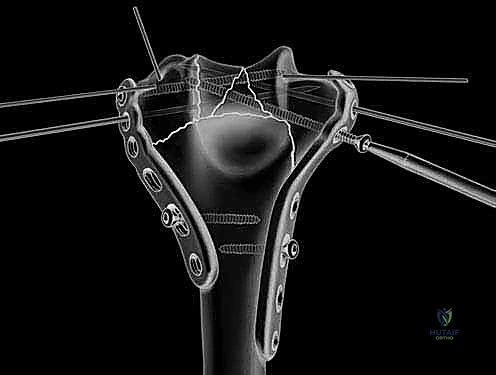

Definitive osteosynthesis is achieved through the application of dual pre-contoured anatomical plates. Following the principles of parallel plating, a plate is applied to the medial ridge and another to the lateral ridge of the distal humerus. The plates are positioned to maximize screw purchase in the distal articular block; ideally, multiple screws should interdigitate through the articular fragments, creating a "rebar" effect. The plates must be compressed to the bone using standard lag techniques or articulated tension devices before deploying locking screws. The stability of the construct is then rigorously tested by taking the elbow through a full, unhindered range of motion. Finally, the olecranon osteotomy is meticulously repaired using the previously drilled lag screw supplemented with a figure-of-eight tension band wire, or via a dedicated proximal ulna locking plate, ensuring rigid fixation to allow for immediate postoperative rehabilitation.